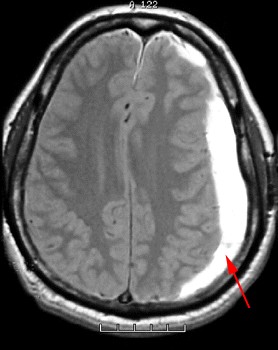

뇌 자기공명영상(MRI)는 뇌의 구조와 기능을 3차원적으로 보여주고, 뇌 컴퓨터단층촬영(CT)는 뇌의 구조를 2차원적으로 보여줍니다. 급성 경막하 출혈에서는 CT와 MRI 검사를 해서 뇌 출혈의 정도와 부위를 파악하게 됩니다. 혈액 검사를 통해 혈액응고 장애가 있는지 유부를 판단합니다.